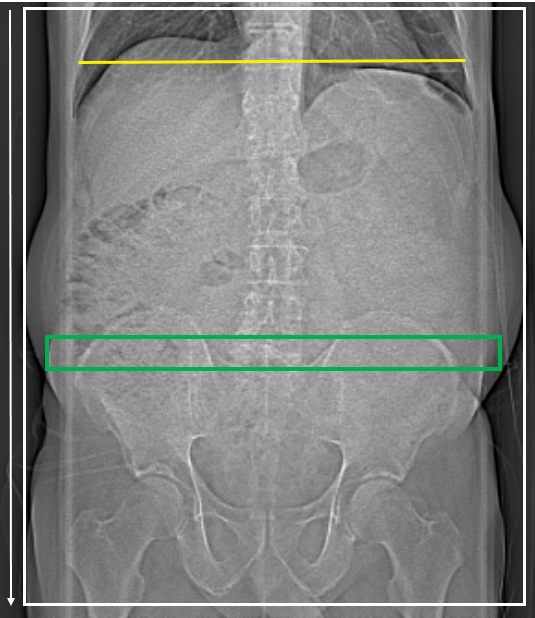

Protokoll där tunntarmen fylls ut med neutralt kontrastmedel (Movprep), tillförd via nasojejunal sond. K-serie över hela buken (i något tidigare kontrastfas än vid "Buk K" för optimal uppladdning av tarmväggen)